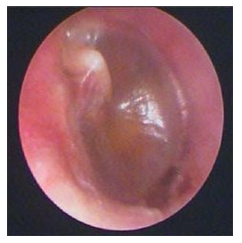

南京治疗中耳炎好的医院是哪家?化脓性中耳炎病情,主要症状为鼓膜穿孔等,如果耳内炎症存在并且耳内有积液,是不会推荐患者进行鼓膜修补的防止病情复发还是需要进行鼓膜穿孔,造成二次伤害.... [详情] 文章日期 :17-03-23

化脓性中耳炎的检查诊断

化脓性中耳炎对人体的危害很大,不及时检查治疗伤害比较大,如何才能减轻痛苦呢?化脓性中耳炎越拖病情只会比较严重,及时治疗才是明智的选择,在治疗前化脓性中耳炎会有检查诊断呢?下面将带大家了解与化脓性中耳炎检... [详情] 文章日期 :16-11-05